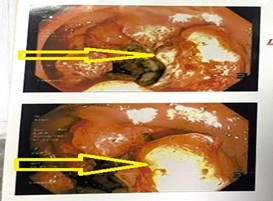

Nội soi đại trực tràng: Đèn soi đi đường hậu môn nhân tạo, ngay dưới hậu môn nhân tạo có khối sùi loét chiếm gần hết chu vi, phần đại trực tràng còn lại không thấy tổn thương.